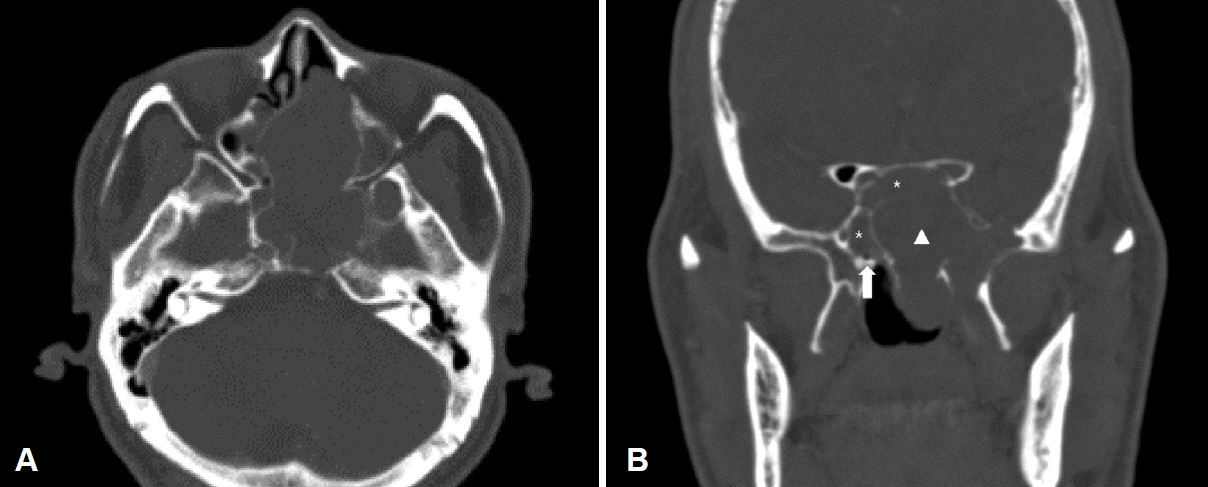

Fig. 2.

Preoperative contrast-enhanced CT revealed well-defined hypodense mass in the left nasal cavity. The lesion of the nasal cavity showed an expansive growth without bone invasion. Axial view (A), coronal view (B). Both sphenoid sinuses (asterisks), right vidian canal (arrow), and nasal cavity mass (arrowhead).